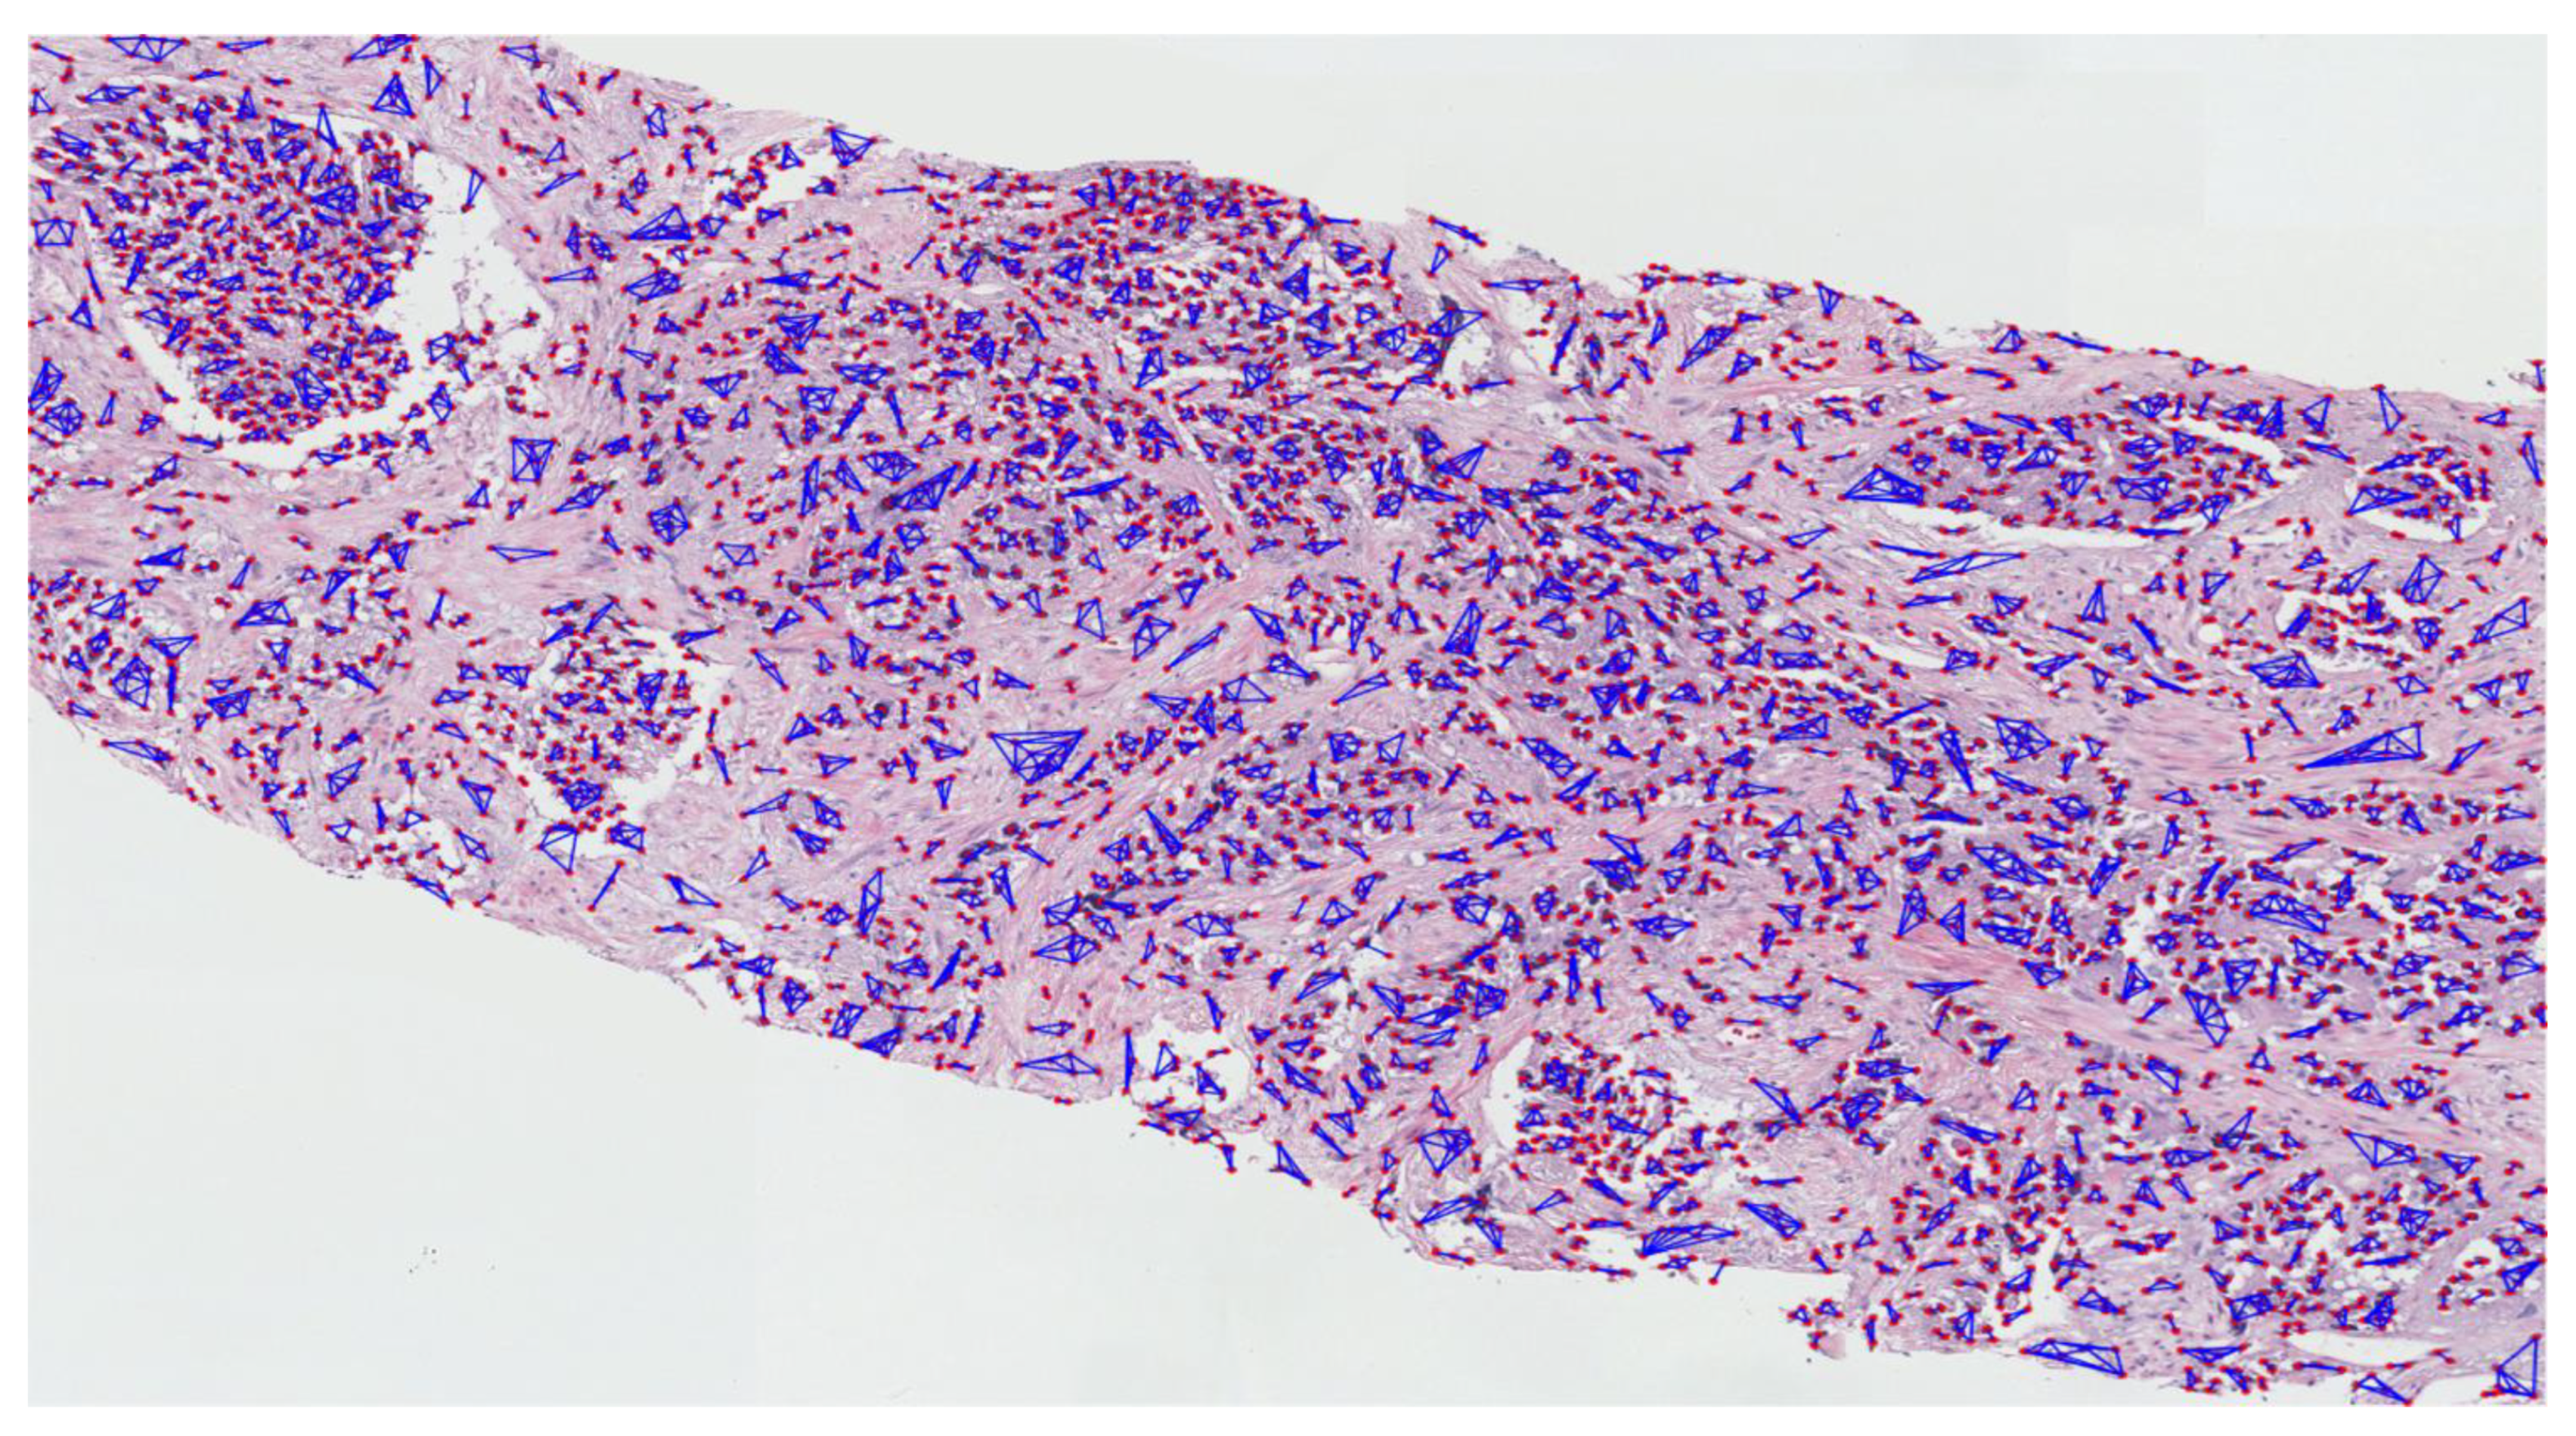

The MST cluster analysis method was applied on the PCa tissue samples of dataset 1 and dataset 2, and the visualization results of intra- and inter-cluster MST are shown in Figure 12. From the following figure, we can analyze that the structure and shape of the clusters in each grade are different from each other. It is quite challenging for researchers and doctors to analyze the microscopic biopsy images of PCa and identify suitable biomarkers compared to other common cancers.

Figure 12.

The visualization of intra- and inter-cluster MST graphs. (a–c) The intra-cluster MST of grade 3, grade 4, and grade 5, respectively. (d–f) The inter-cluster MST was generated from a, b, and c, respectively. The dotted red circle indicates the cluster of cell nuclei. Different color lines in a-c and d-f indicate intra- and inter-clusters, respectively.

The gold standard for the diagnosis of prostate cancer is a pathologist’s evaluation of prostate tissue. To potentially assist pathologists, DL-based cancer detection systems have been developed. Many of the state-of-the-art models are patch-based convolutional neural networks. Patch-based systems typically require detailed, pixel-level annotations for effective training. However, such annotations are seldom readily available in contrast to the clinical reports of pathologists, which contain slide-level labels. Our study sliced annotated and graded images from the pathologist, and we use an MST algorithm to perform cluster analysis and extract significant information for AI classification. The proliferation and cluster structure of cell nuclei, as shown in Appendix A, Figure A4 (Gleason pattern 3), Figure A5 (Gleason pattern 4), and Figure A6 (Gleason pattern 5), will help the pathologist to identify, classify, and grade more precisely the Gleason score assignment in the light of heterogeneity and variability.

The pathology annotated WSIs used in this research to analyze the pattern and community structure of cell nuclei in grades 3, 4, and 5, shown in Figure A1, Figure A2 and Figure A3, respectively. The cluster analysis was performed successfully on histological images of PCa. For visualization of the community structure of cell nuclei, we plot the clusters in the annotated regions of grade 3, grade 4, and grade 5 in WSIs, shown in Figure A4, Figure A5 and Figure A6, respectively.